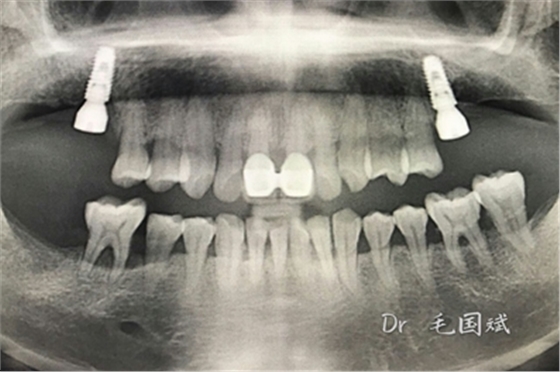

毛國(guó)斌種植病例——群討論分享

Screenshot_2017-04-25-09-45-02.pngScreenshot_2017-04-25-09-46-19.pngScreenshot_2017-04-25-09-51-57.pngScreenshot_2017-04-25-09-52-41.pngScreenshot_2017-04-25-10-06-38.pngScreenshot_2017-04-25-10-09-20.png

Screenshot_2017-04-25-10-12-47.pngScreenshot_2017-04-25-10-16-29.pngScreenshot_2017-04-25-10-19-08.pngScreenshot_2017-04-25-10-22-02.pngScreenshot_2017-04-25-10-26-11.pngScreenshot_2017-04-25-10-26-35.png

Screenshot_2017-04-25-10-34-15.pngScreenshot_2017-04-25-10-37-02.pngScreenshot_2017-04-25-10-38-17.pngScreenshot_2017-04-25-10-43-56.pngScreenshot_2017-04-25-10-45-02.png

mmexport1493090938783.jpgmmexport1493090943165.jpg

mmexport1493090947523.jpgmmexport1493090952079.jpg

mmexport1493090960504.jpgmmexport1493090963186.jpg

mmexport1493090967371.jpgmmexport1493090969886.jpg

mmexport1493090972304.jpgmmexport1493090974802.jpg

mmexport1493090981101.jpg

mmexport1493090983321.jpgmmexport1493090991830.jpg

mmexport1493090994026.jpgmmexport1493090985721.jpg

mmexport1493091008273.jpgmmexport1493091010574.jpg

江思玉整理群種植病例